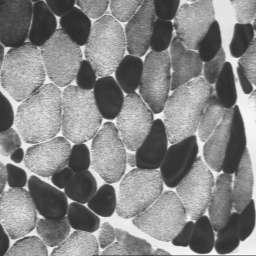

Imagen microscópica de fibras musculares (corte)